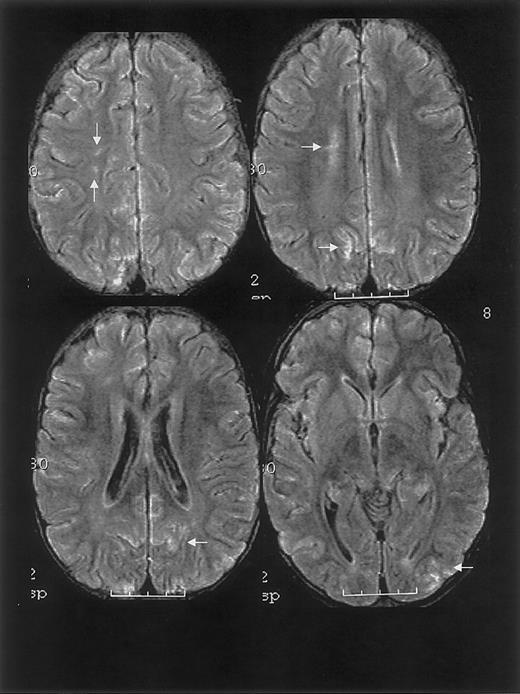

One year prior to ACS episode, the patient had a normal MRI study. MRI on hospital day 20 and 2.5 months following discharge revealed findings consistent with RPLS and silent cerebral ischemia (Figure 1).

MRI findings for case 1.

Multifocal areas of fluid-attenuated inversion recovery (FLAIR) T2-weighted signal abnormality in the subcortical white matter and overlying gray matter of the frontal, parietal, and occipital lobes (bottom).